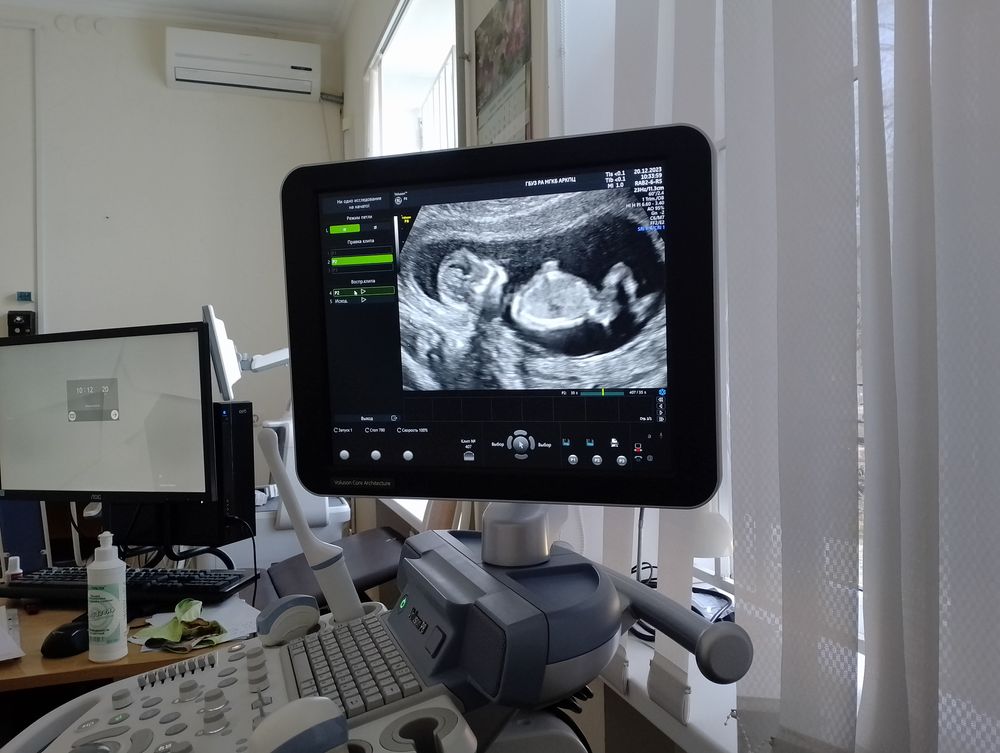

Пол ребенка по УЗИ в 12.5 недель сказали с большой вероятностью мальчик, кто разбираеться в половых бугорках

А вам столько лет? Я так поняла, что у нас в Москве всех старше 35 на НИПТ приглашают и там пол будет 100%. Я тоже в 12 недель на бугорке гадала, тоже мальчика предположили на скрининге, а через пару дней на НИПТ вызвали и через недельку подтвердилось, что точно мальчик.

20.12.2023